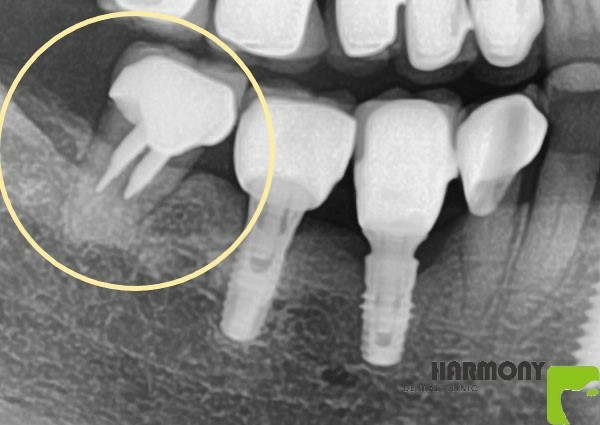

患者牙齒因為牙周病被拔除

別院諮詢時 建議拔牙後植牙

我們選擇了利用矯正的方式重建